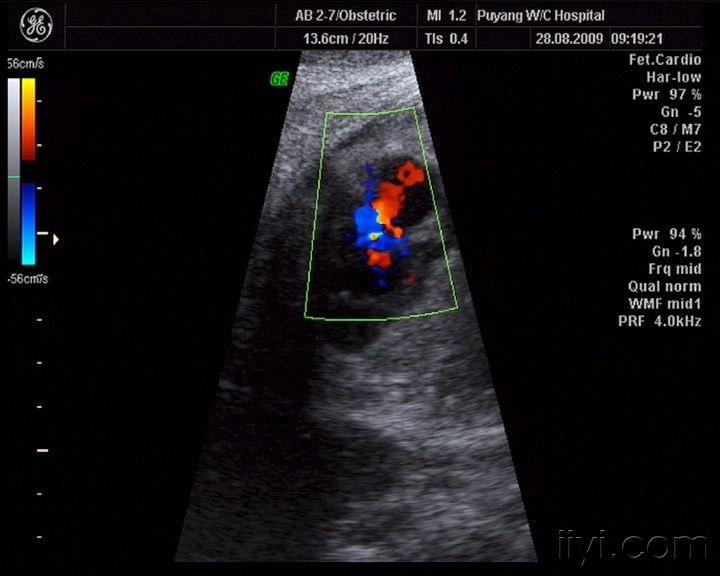

三尖瓣反流

三尖瓣返流

胎儿心脏三尖瓣少量反流